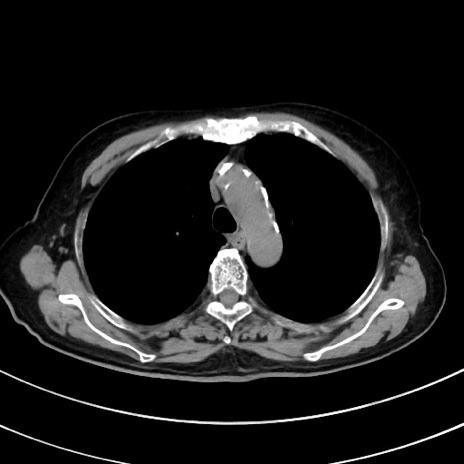

冠状断像